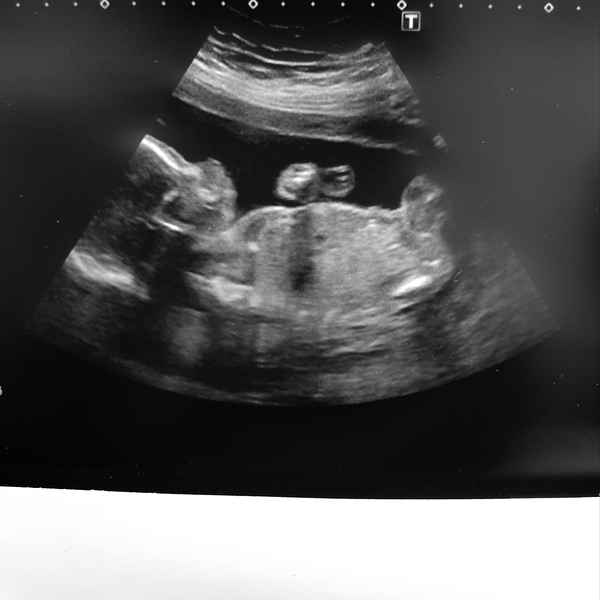

Well scan went well with a very active baby so took ages for the sonographer to get all the measurement but we have a very healthy little boy who wasnt afraid to show he was certainly a boy she said haha!💙

Jowd92 · 15/08/2019 11:38

Forgot to attach the scan